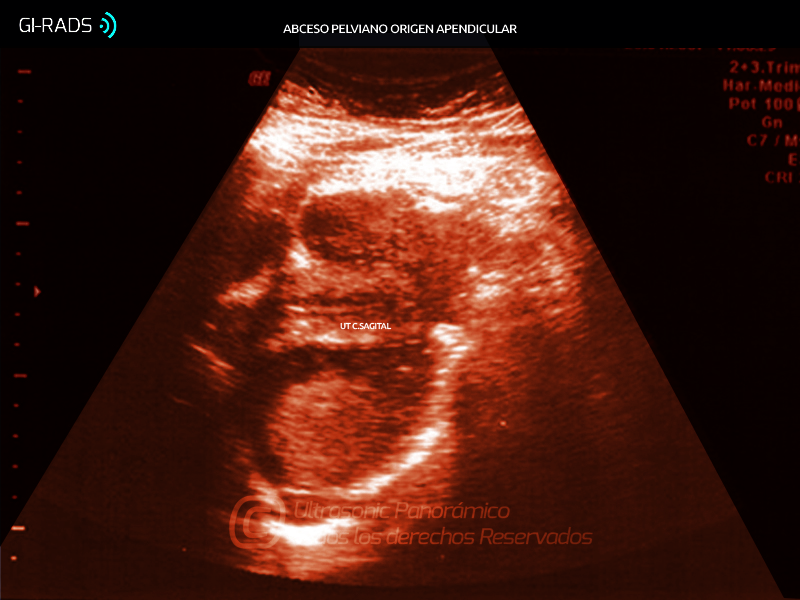

Patologías Benignas – Patología Extra-Ginecológica

• Patologías Benignas – Patología Extra-Ginecológica